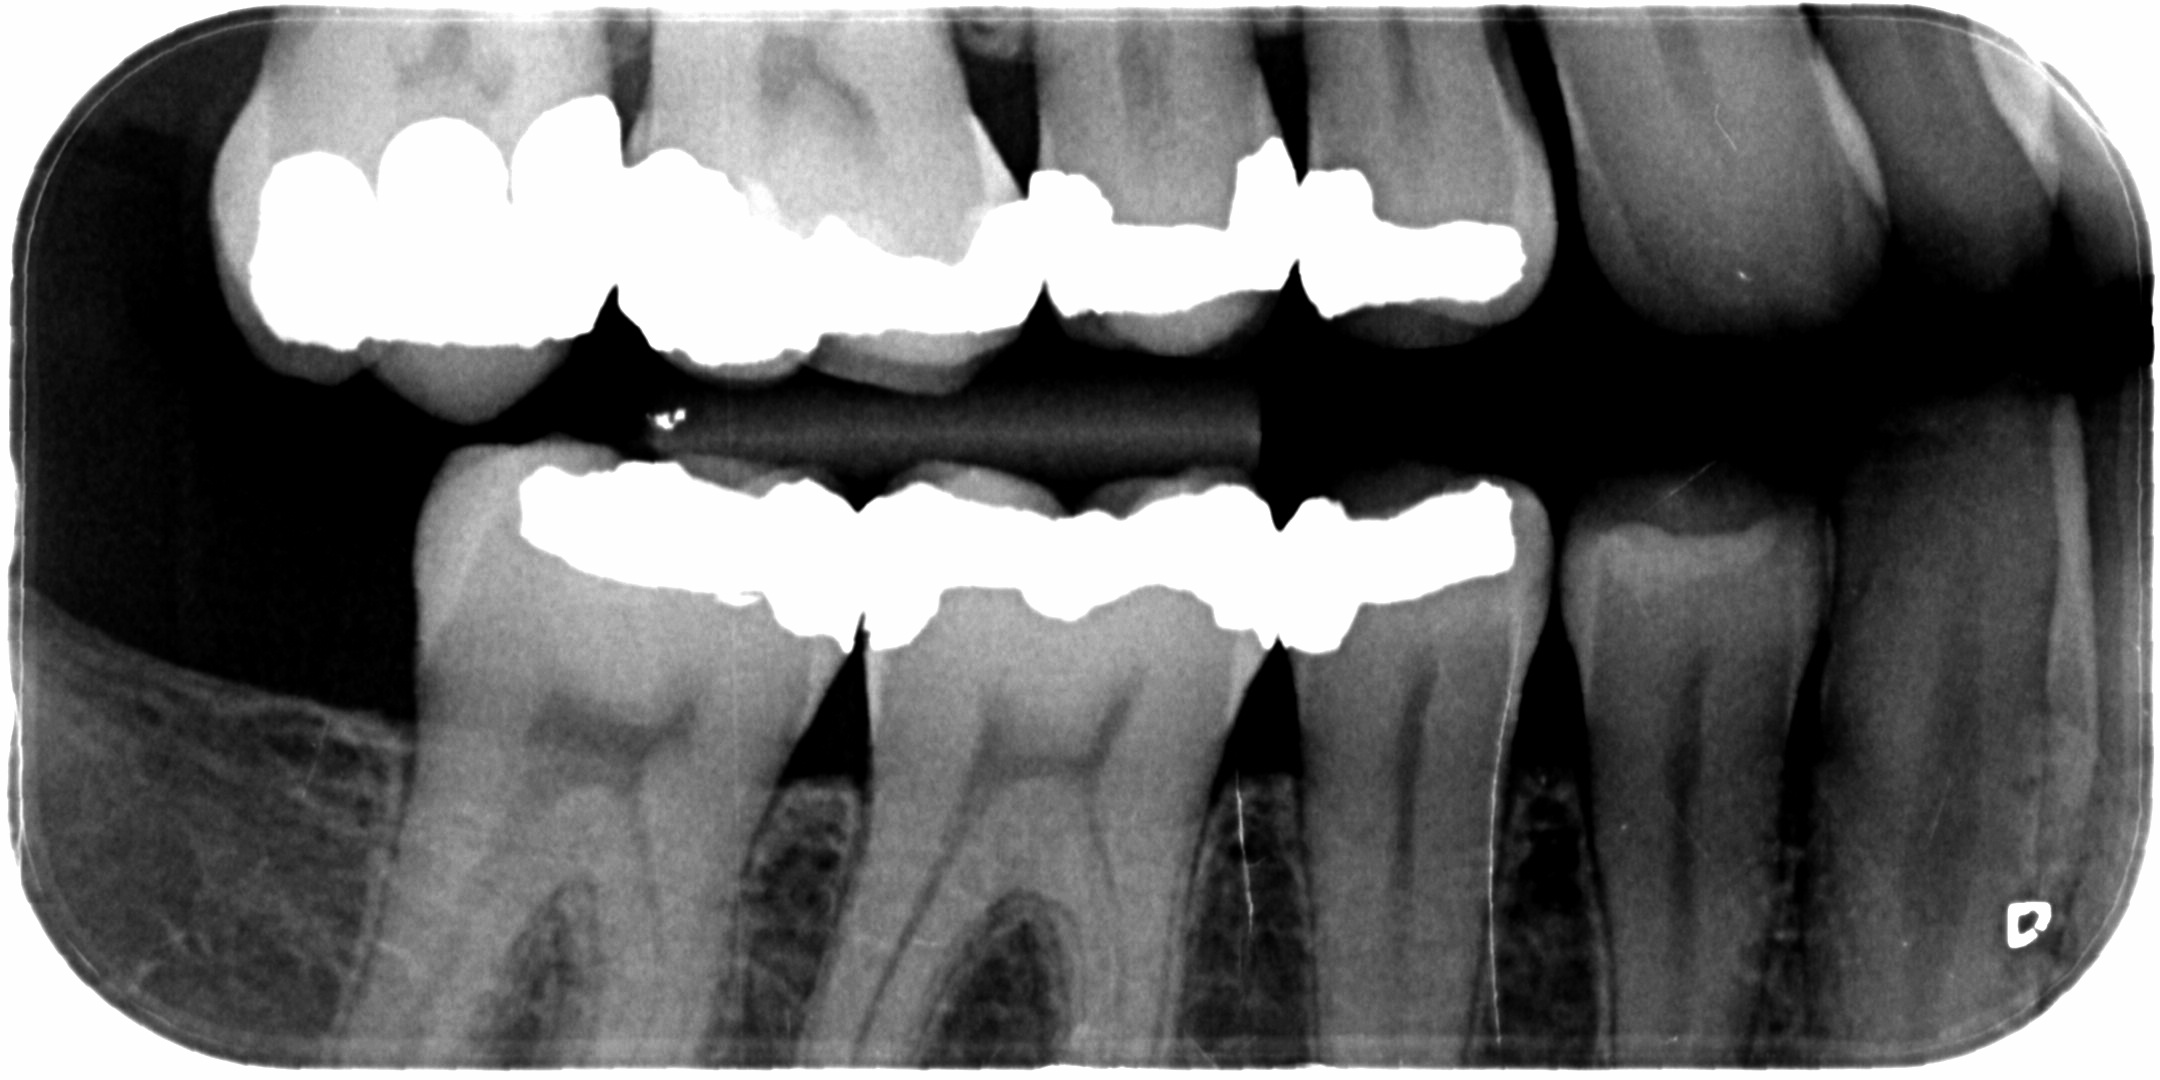

Hoe zien gaatjes eruit in je kiezen? Een gaatje in een tand of kies kan eruitzien als een donker of juist wit vlekje. In de beginfase van een gaatje is er meestal geen pijn. Echter, als de tandbederf verergert, kan het wel gevoelig worden en ongemak veroorzaken bij het eten of drinken van warme of koude voedingsmiddelen en drankjes.. Het ontstaan van een gaatje en andere aandoeningen. Eet je vaak suiker, dan doet het proces van verzuring zich dus ook regelmatiger voor. Er kunnen dan gaatjes ontstaan. Poets je daarnaast niet goed, dan heb je sneller last van tandsteen. Deze twee aandoeningen kunnen samen uitmonden in kiespijn en uiteindelijk zelfs in een wortelpuntontsteking.